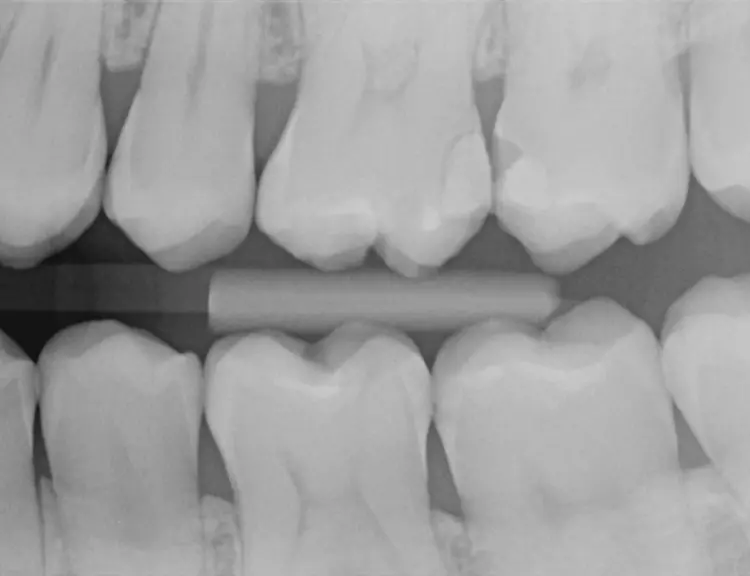

Bei einem 31-jährigen Patienten ohne Vorerkrankungen mussten aufgrund primärer und sekundärer Karies mehrere Seitenzahnfüllungen ersetzt und erneuert werden. Die Zähne 26 und 27 waren mit älteren Kompositfüllungen versorgt.

Die vorhandenen Restaurationen waren defekt und undicht, sodass sich Speisereste einlagerten (Abb. 1). Die Bissflügelaufnahme bestätigte den klinischen Befund (C2). Die Sekundärkaries hatte nur wenig das Dentin infiltriert (Abb. 2).